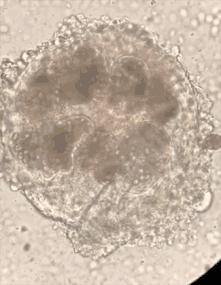

虽然知道了病因,但手术还是不能轻易进行。因为是包虫病,京京的囊肿里肯定有着大量的棘球蚴幼虫。如果手术中不慎导致囊壁破裂,那么囊液里的棘球蚴就会给胸腔和腹腔带来感染。严重时可能会导致过敏性休克,甚至是死亡!

虽然手术前,都做好了心理准备,但看着乳白色的包虫不停蠕动,和从囊肿里抽出的1000多毫升虫液,在场的人无一不感到头皮发麻。